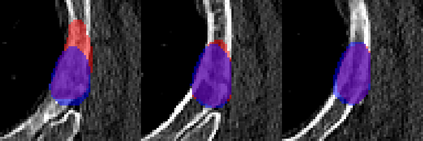

Rib fractures are a common and potentially severe injury that can be challenging and labor-intensive to detect in CT scans. While there have been efforts to address this field, the lack of large-scale annotated datasets and evaluation benchmarks has hindered the development and validation of deep learning algorithms. To address this issue, the RibFrac Challenge was introduced, providing a benchmark dataset of over 5,000 rib fractures from 660 CT scans, with voxel-level instance mask annotations and diagnosis labels for four clinical categories (buckle, nondisplaced, displaced, or segmental). The challenge includes two tracks: a detection (instance segmentation) track evaluated by an FROC-style metric and a classification track evaluated by an F1-style metric. During the MICCAI 2020 challenge period, 243 results were evaluated, and seven teams were invited to participate in the challenge summary. The analysis revealed that several top rib fracture detection solutions achieved performance comparable or even better than human experts. Nevertheless, the current rib fracture classification solutions are hardly clinically applicable, which can be an interesting area in the future. As an active benchmark and research resource, the data and online evaluation of the RibFrac Challenge are available at the challenge website. As an independent contribution, we have also extended our previous internal baseline by incorporating recent advancements in large-scale pretrained networks and point-based rib segmentation techniques. The resulting FracNet+ demonstrates competitive performance in rib fracture detection, which lays a foundation for further research and development in AI-assisted rib fracture detection and diagnosis.